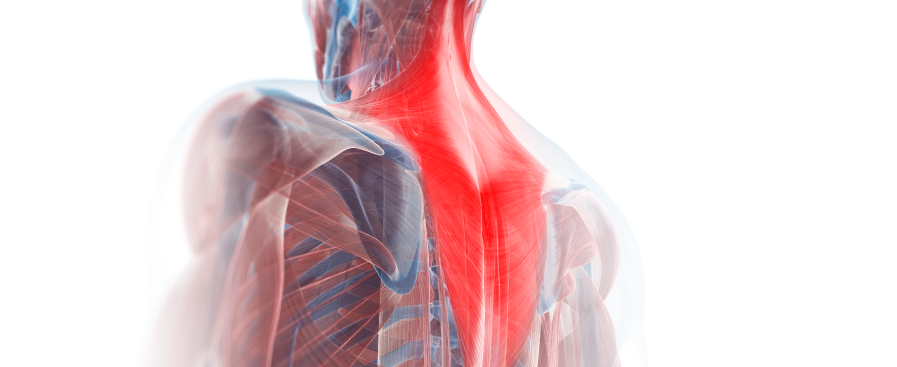

Sportverletzung die nicht ausheilt? Langwieriger Verlauf?

Dies alles sind Anzeichen einer beginnenden Schmerzchronifizierung. Dem sollten Sie vorbeugen. Konsequente Schmerztherapie verhindert einen protrahierten Verlauf -

Verhinderung Chronischer Rückenschmerzen:

Konsequente Schmerztherapie bei akuten Rückenverletzungen. Rehamaßnahmen können frühzeitig bei guter Schmerzkontrolle begonnen werden.